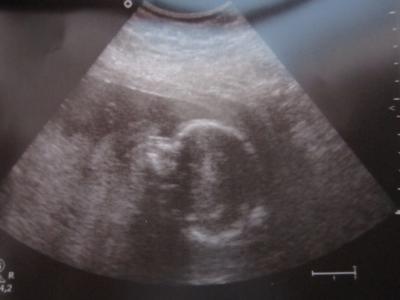

Einen wunderschönen Guten morgen alles zusammen... Ich hoffe euch allen geht es soweit ganz gut und eure Zwerge machen sich schön bemerkbar in euren Bäuchen. Wir hatten heute morgen VU und das 2.Screening und was soll ich sagen es ist alles perfekt. Alle Organe sind vorhanden und arbeiten. Die Aufteilung ovn Gehirn und Herz ist so wie es sein soll. Babylein wird vernünftig versorgt. Meine wie auch ihre Aorta arbeiten perfekt. Es bleibt bei einem Mädchen. Bin heute 22+2 und sie ist ca. 28cm groß und wiegt ca. 520gr. Meine erste Tochter hatte zum gleichen Zeitpunkt genau die gleichen Werte. Haut um Bauch und Rücken ist geschlossen und eine Kiefer-Gaumen Spalte konnte ausgeschlossen werden. Rund um ist die Kleine perfekt und die Ärztin super zufrieden. CTG wurde auch wieder gemacht aber nur wegen Wehen aber auch dort sind keine vorhanden. Ach einfach schön.. So gestern habe ich dann noch mein neues Stillkissen bekommen was man später auch als Sitzkissen verwenden kann. Wenn man das Stillkissen als U machen kann man so ne Stofflasche rausholen und befestigen und dort das Babylein reinlegen und gleichzeitig mit so einer Art gürtel befestigen. Hab euch mal den Link dazu rausgesucht. Vielleicht gefällt das ja jemanden. Der Stoof ist total weich und ich bin super zufrieden.. http://www.mytoys.de/candide-Liege-Stillkissen-Multirelax-rosa-grau/Stillkissen/KID/de-mt.ba.ca01.05/2260676 So nun genug von uns. Wünsche euch allen noch einen schönen Tag. Passt auf euch auf. Ganz liebe Grüße Jeannett

Bild zu Guten morgen VU und 2.Screening hinter uns - Forum für Februar - Mamis